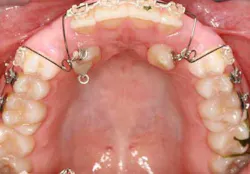

When a full permanent dentition is present (with the exception of impacted canines), the labial/palatal position of the canine will have an influence on what the provider can do. (1) Arguably, obtaining a CBCT is considered mandatory and will allow for a more inclusive treatment plan creation. If angulation is favorable, then consideration to remove the primary canine and wait six months to see if there is movement of the permanent canine is an option. If extraction of the canine(s) is needed, then a premolar substitution, which is dependent on occlusion, can be used in the space. An implant can also be an appropriate alternative. When pulling a canine into the occlusal arch, there is risk involved. Trauma to adjacent teeth (root resorption) and ankylosis are some of the most common complications.The patient was put in full orthodontics and referred to a surgeon for extraction of the primary canines, exposure, and placement of retention on the impacted canines to pull them directly down from their current position.

A ballista appliance was used to prevent a facial pull of the canines in order to avoid and prevent resorption of the roots of the lateral incisors. As movement progressed over the course of the next year, eruption of the canines was considered a success. Once in position, they will be pulled facially into occlusion.